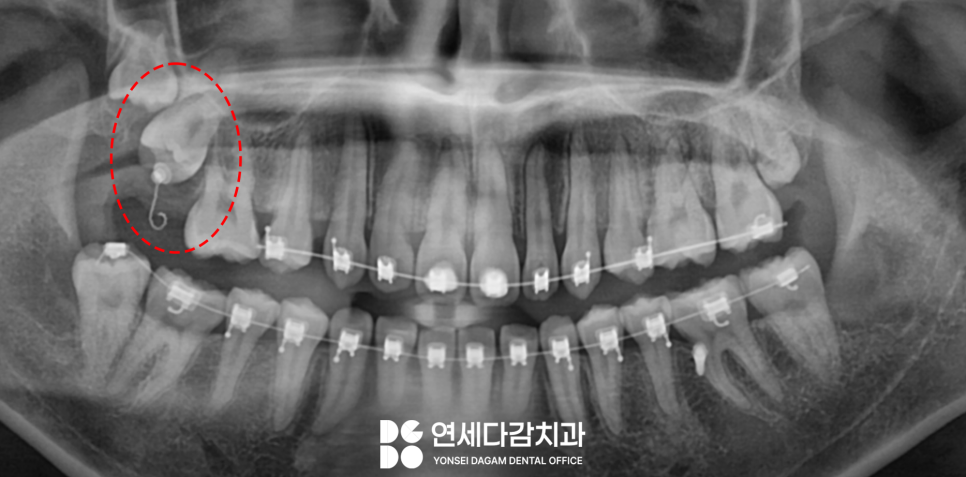

오금동 치과 에서 촬영한

파노라마 사진을 보면,

사랑니 4개가 모두

존재하고 있습니다.

오금동 치과 에서는 교정 시작 전

하악 사랑니 2개를 먼저

빼는 것을 계획하였습니다.

따라서 CT를 통해 3차원적으로

해부학적 구조물을 정밀하게

분석해야 됩니다.

오금동 치과 에서는 우선 아래 치아부터

진행하기 위해 오른쪽을

먼저 살펴봤습니다.